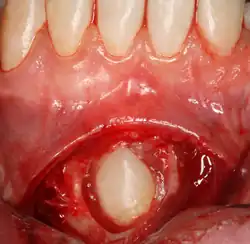

Pericoronitis

Pericoronitis is an infection of the soft tissue that covers the crown of an impacted tooth and is usually caused by the normal oral microbiota. For most people there exists a balance between the host defenses and the oral micriobiota but if the host defenses are compromised like during minor illness such as influenza or an upper respiratory tract infection, pericoronitis results. Another common cause is entrapment of food beneath the gum flap (also called an operculum). Pericoronitis can present as a mild infection or severe infection. In its mildest form it is just a localized tissue swelling and soreness whereas in severe forms the swelling is slightly larger even sometimes creating trismus (difficulty opening the mouth).